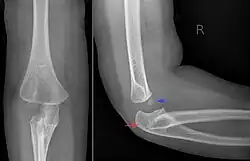

Die Diagnose ergibt sich meist aus dem Röntgenbild, Sonographie und Kernspintomographie können weitere Einzelheiten dokumentieren.

Bei einseitiger Luxation, insbesondere nach ventral, ist die Abgrenzung zu einer erworbenen Ausrenkung sehr schwierig.[1] Nach McFarland sprechen folgende Kriterien für eine kongenitale Luxation:[6]

- Hypoplasie oder Fehlen des Capitulum humeri

- Längenunterschied der Unterarmknochen

- konvexe Wölbung, Verlängerung und Verschmächtigung des Radiuskopfes

- konkave Form der Ulna zum Radiuskopf

- Hypoplasie der Trochlea mit prominentem ulnaren Epikondylus